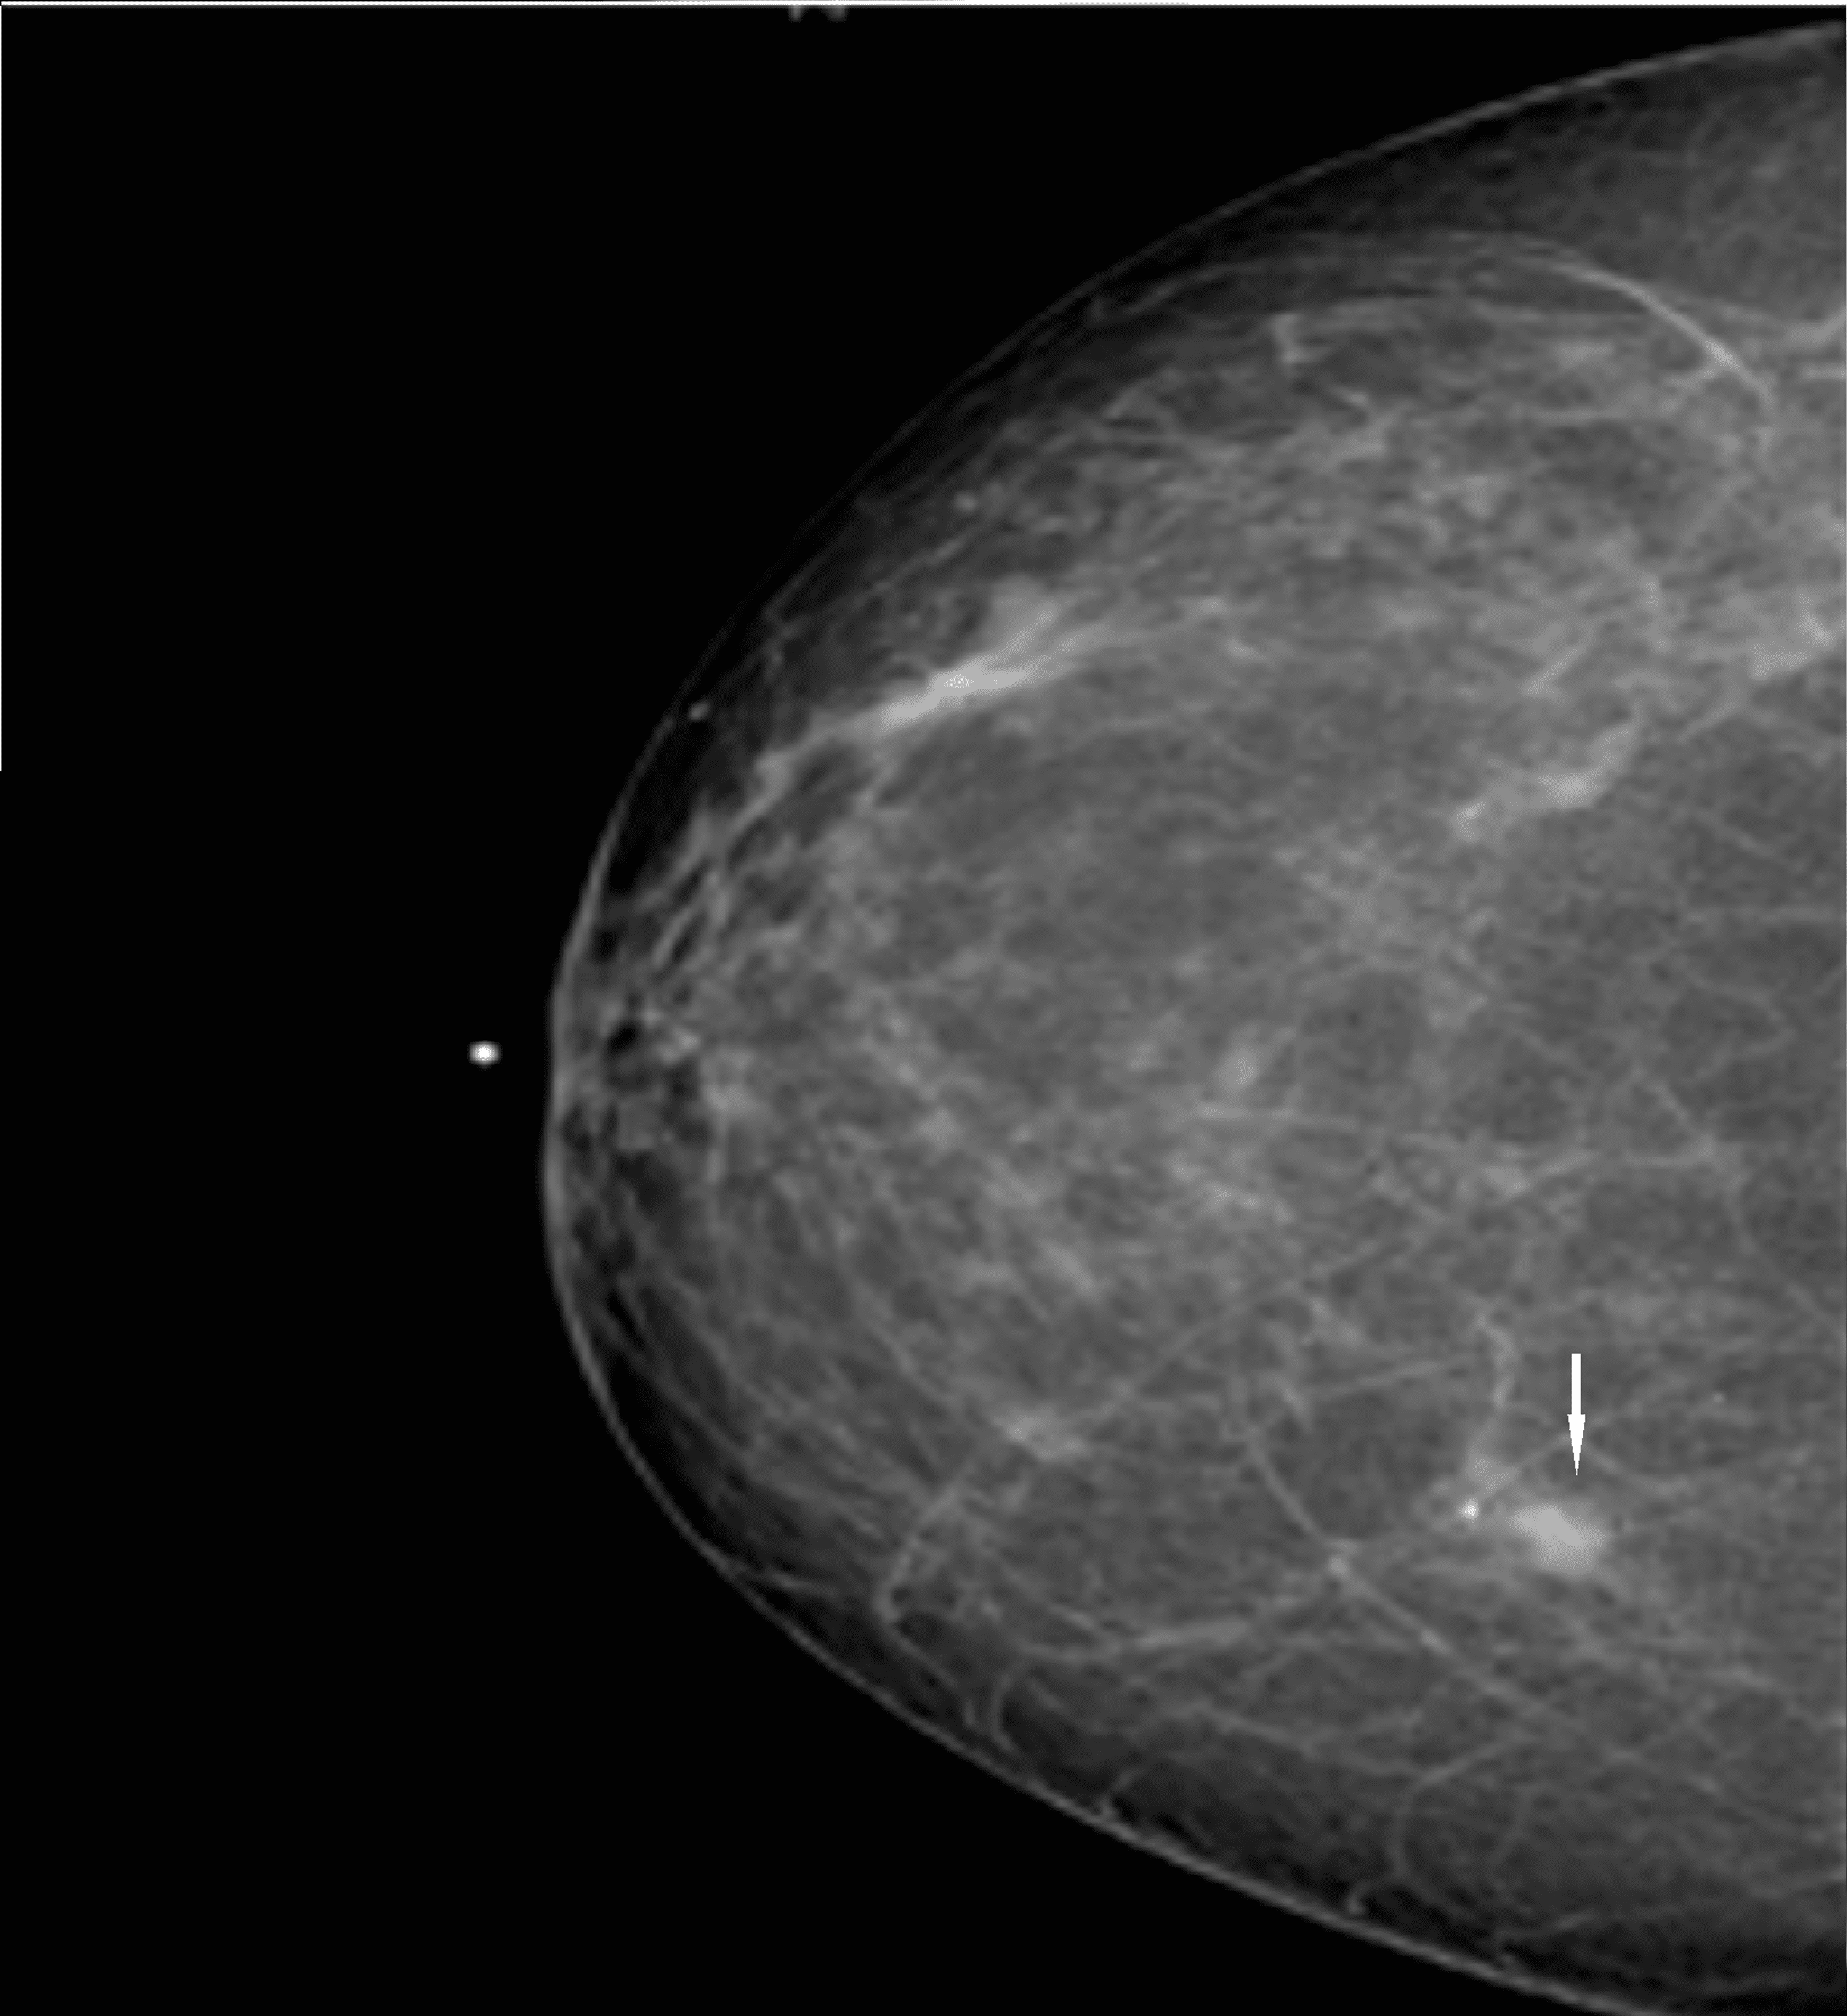

Breast Cancer Scars; port, lumpectomy & mastectomy scars healed, from a www.youtube.com64 | Radiology Key

64 | Radiology Key radiologykey.comlumpectomy scars mlo mammography fig digital